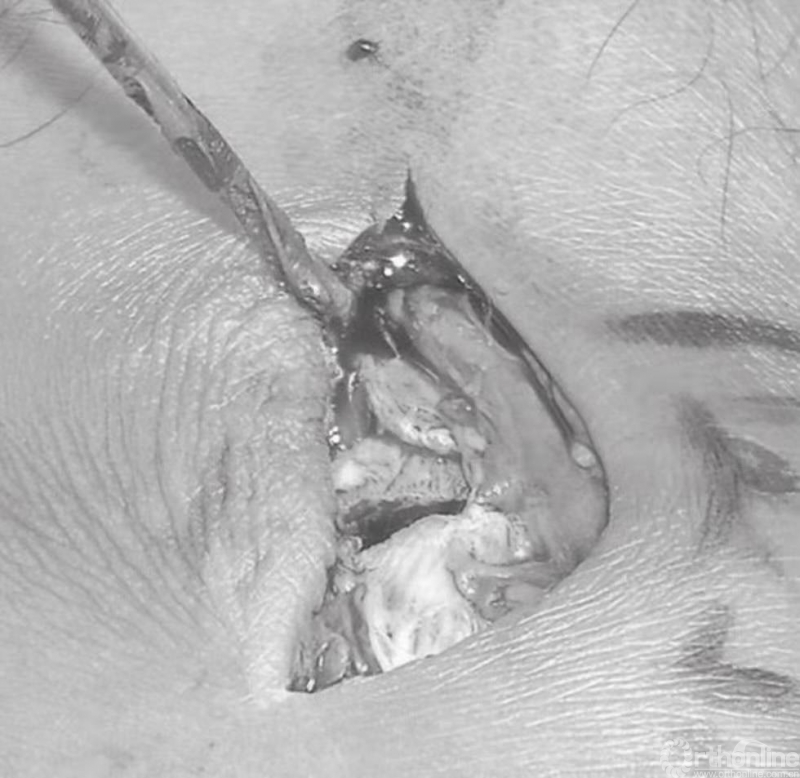

内踝骨折中通常会伴有骨膜撕裂(图11)。这些骨折病例大多数均存在骨膜的介入,这便造成了愈合困难,可能导致骨不连。应将骨膜抬离骨折端,并清理折断表面的血块。将骨折片向远端回缩,以观察关节。在移除关节内所有的游离骨块后,用盐水清洗关节(图12)。

图11 骨膜撕裂及骨折间隙

图12 在移除关节内所有的游离骨块后,用盐水清洗关节